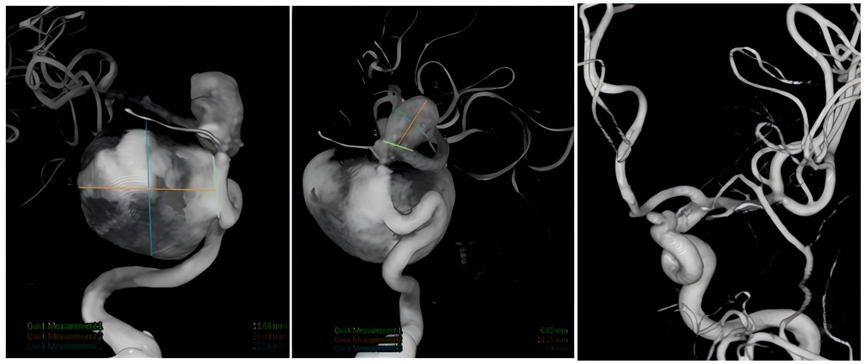

图片

脑血管造影显示双侧颈内动脉多发动脉瘤

团队经过充分评估后,为陈阿婆量身定制了“两步走”的个性化治疗方案:第一步,先由神经外科主任医师戴炯领衔的神经介入团队,通过微创的支架辅助弹簧圈栓塞术,“拆除”左侧颈内动脉上的动脉瘤,手术在3月中旬完成,术后3个月复查显示左侧动脉瘤已痊愈。第二步,聚焦右侧“主战场”。鉴于右侧两个动脉瘤体积巨大、瘤颈宽、形态不规则、位置毗邻颅底且彼此靠近,常规方法风险高、效果有限。血流重建团队果断决策,为陈阿婆实施颅内外高流量血管搭桥术。

高精手术除隐患,“拆弹”成功迎新生

7月中旬,手术如期进行。张晓华主任医师带领血流重建团队成功完成了“右侧颈外动脉-桡动脉-大脑中动脉高流量血管搭桥术”,术中及术后造影结果令人振奋:桥血管通畅无阻,动脉瘤内血流显著瘀滞(预示其将逐渐闭塞),而右侧大脑半球的血流灌注得到了完美保护,这标志着右侧颈内动脉上的两颗巨型“炸弹”也被成功“拆除”并永久失效。

术后数字减影血管造影(DSA)显示桥血管通畅